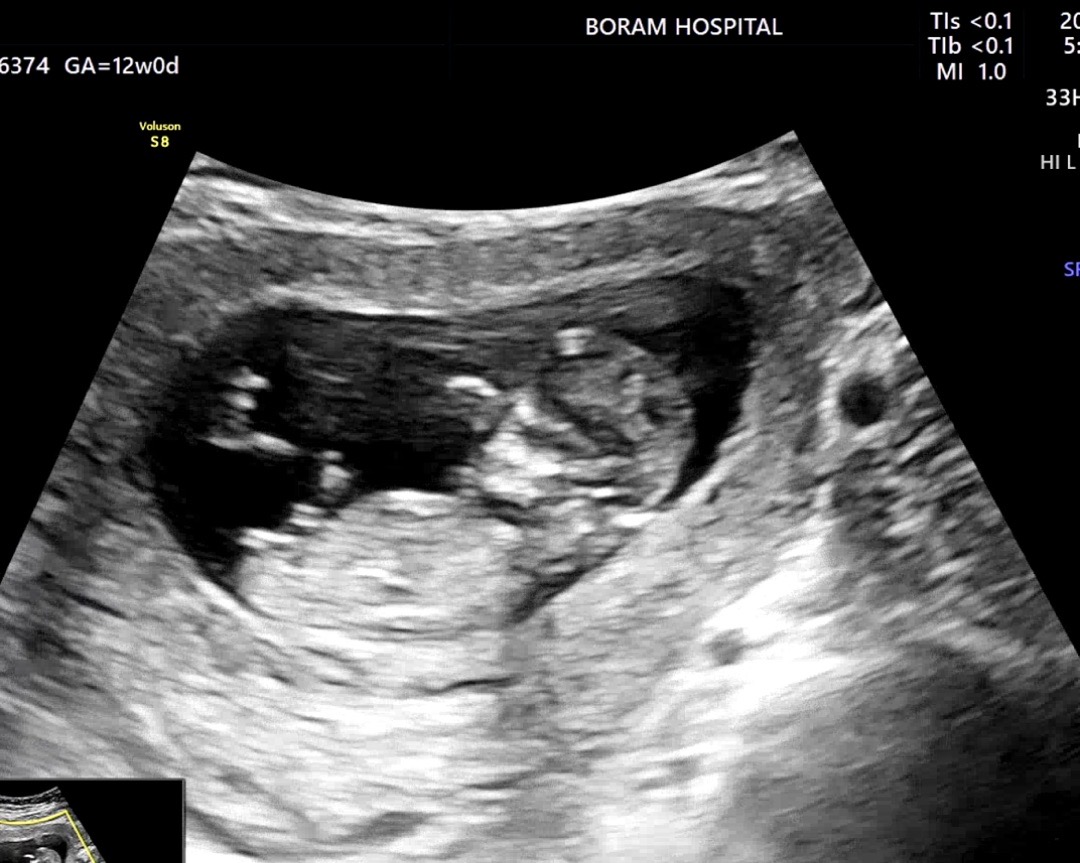

이걸로 보이까요!!?! 딸일까요 아들일까요?!?!🥰